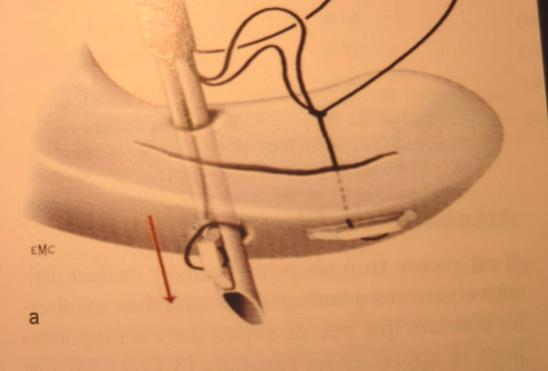

Principes, suites et résultats d’une suture méniscale

En raison du risque de lésions cartilagineuses à long terme dans les suites des méniscectomies sur genou stable ou après reconstruction du LCA, s'est développé le concept de réparation méniscale. Cette réparation repose sur deux principes fondamentaux : un avivement des berges de la lésion pour favoriser la cicatrisation et une fixation primaire stable par une suture.

Sur genou laxe, les lésions méniscales sont le plus souvent représentées par une désinsertion périphérique du segment postérieur du ménisque interne. Malgré leur potentiel de cicatrisation spontanée, elles doivent être diagnostiquées et traitées. L’arthroscopie permet d’évaluer la taille et la stabilité de la lésion. Le ménisque devra être suturé, si la désinsertion fait plus de 10 mm de large ou si le ménisque désinséré peut être mobilisé sous le cond yle (Figure 3). Dans le cas contraire, un simple avivement de la lésion suffit pour permettre la cicatrisation. Que la laxité soit récente ou ancienne, il est souhaitable de réaliser dans le même temps que la suture méniscale, une réparation du LCA car les chances de cicatrisation sont de 90%.

Les sutures méniscales utilisent des fils ou des implants mis en place sous arthroscopie. Le dispositif le plus fiable actuellement est le FAST FIX ( Figure 9).

Figure 9 : suture méniscale par fil tout en dedans (FAST FIX )